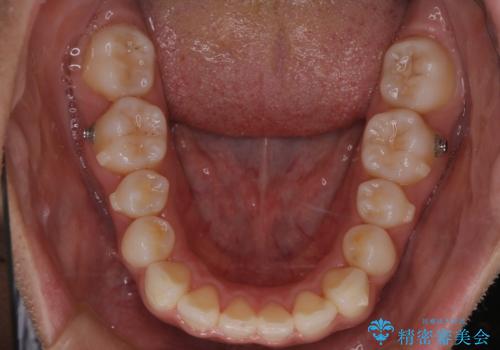

【インビザライン】前歯の後戻りを再矯正

- 前歯が出ていることを主訴に来院されました。検査の結果、口元が標準より出ているわけではなかったため今回はIPRと拡大をし、非抜歯で治療を行いました。

非抜歯でも歯軸の向きを改善したことで前歯が下がり、出っ歯に見えてしまうという主訴が改善しました。